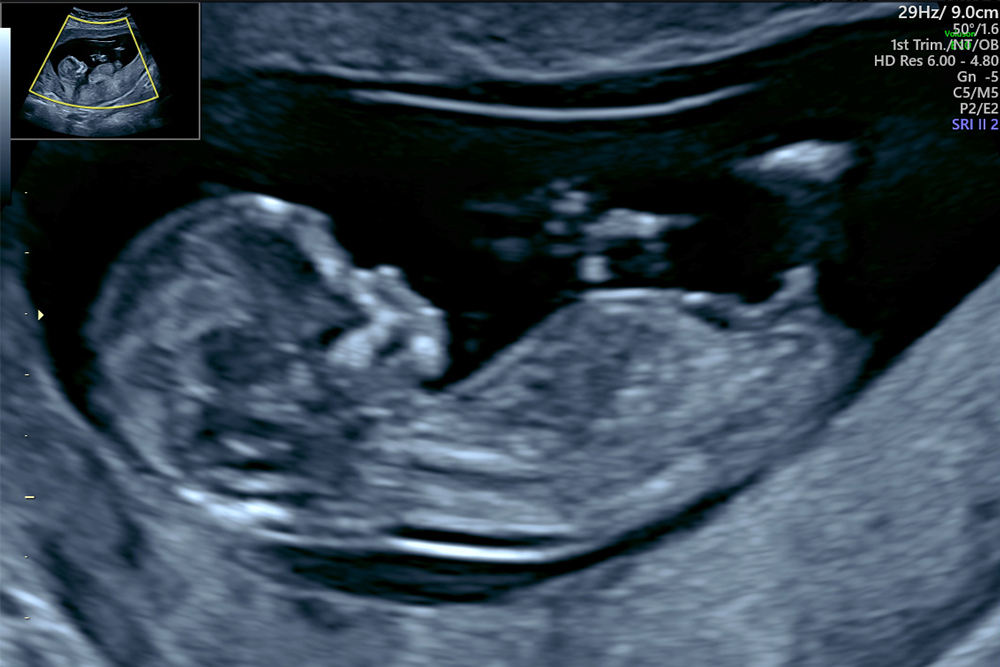

超音波検査、または胎児超音波検査は、音波を使用して子宮内で発育中の胎児の画像を作成する手順です。

胎児超音波スキャン中、超音波検査技師はトランスデューサーを使用して体内に音波を送ります。これらの波は、エコーとして戻ってくる前に、体内の臓器や組織と相互作用します。トランスデューサーは、これらのエコーを体内で起こっていることの画像に変換します。

超音波検査により、人々は動いている胎児を見ることができます。ただし、超音波検査では動きだけではありません。これらは胎児の発育や妊娠の健康状態に関する情報を提供し、治療が必要な可能性のある問題を特定するのに役立ちます。